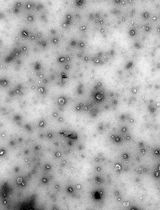

Dynamic light scattering analysis showed that the average sizes for blank nLNPs (Figure 3) and IL-22/nLNPs (Figure 5) are 189.9 ± 69.3 and 184.2 ± 84.96 nm, respectively, based on triplicate measurement.

Figure 3. Measurement of size in blank nLNPs. Particle size was determined to be 189.9 ± 69.3 nm in diameter.